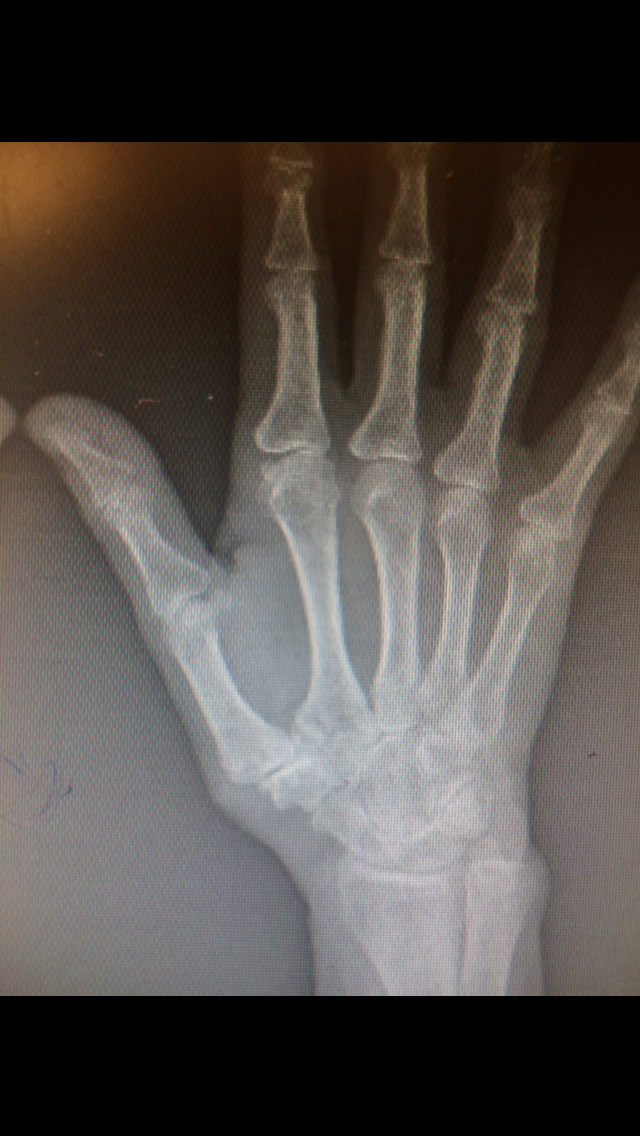

- Case 1